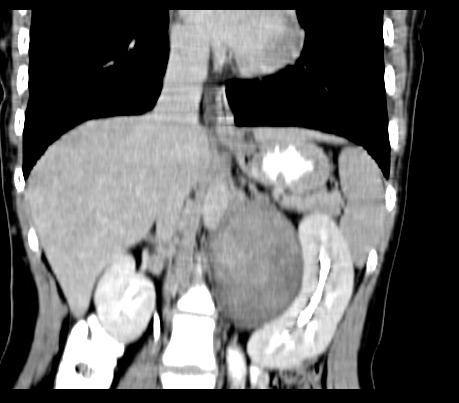

静脉期

延时5分钟

延时10分钟

重建

神经纤维瘤病